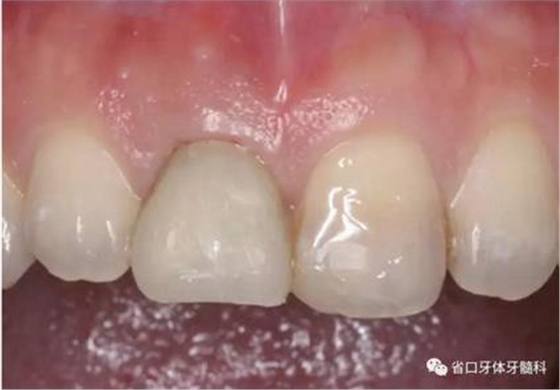

(4)最終修復(fù)與隨訪:經(jīng)過3個月左右的塑形,上頜右側(cè)中切牙臨時修復(fù)固位良好,菌斑控制良好,近遠(yuǎn)中齦乳頭充盈良好,齦緣水平及形態(tài)與 鄰牙相對稱。牙齦塑形穩(wěn)定后,以臨時修復(fù)體制作個性化轉(zhuǎn)移桿并取模轉(zhuǎn)移,并以原廠氧化鋯基臺制備個性化基臺及全瓷冠。正確就位最終基臺,加 力30N·cm。制備粘接代型,去除多余粘接劑,以Unicem粘接固位上頜右側(cè)中切牙全瓷修復(fù)體。固化穩(wěn)定后,再次確定咬合無干擾。最終修復(fù)完成后 隨訪3個月及6個月,上頜右側(cè)中切牙種植修復(fù)固位穩(wěn)定,近遠(yuǎn)中齦乳頭充 盈良好,唇側(cè)齦緣水平穩(wěn)定。

圖30 塑形完成

圖34 負(fù)重3個月后

圖35 負(fù)重6個月后復(fù)診

上頜右側(cè)中切牙修復(fù)體固位良好,牙齦乳頭充盈良好,齦緣水平對稱 修復(fù)體與對側(cè)同名牙協(xié)調(diào)一致。外觀笑容美觀協(xié)調(diào)?;颊邼M意。X線檢查示 上頜右側(cè)中切牙種植體周穩(wěn)定骨質(zhì)包繞,唇側(cè)骨板>2mm,相鄰牙槽骨高度穩(wěn)定,基臺及修復(fù)體就位良好。分別根據(jù)Furhauser的PES和Bulser的WES 進(jìn)行美學(xué)評分,總分值為20,美學(xué)效果良好。